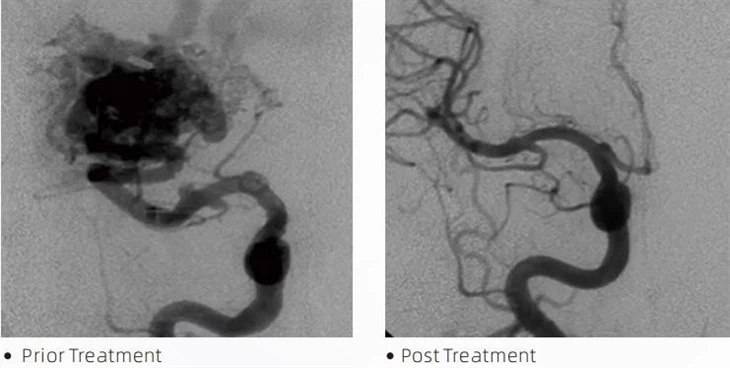

LavaTM embolic glue is a medical device used by interventional neuroradiologists during minimally invasive procedures to treat conditions such as cerebral aneurysms, arteriovenous malformations and tumors. The Lava embolic glue offers multiple benefits to medical professionals and patients alike in terms of safety, ease of use and effectiveness. Lava is able to seal off blood vessels quickly and efficiently. The process involves injecting the glue directly into the targeted vessel, where it polymerizes and hardens into a cast-like mass that fills the aneurysm or malformation. Then it effectively cuts off the blood flow to the lesion, preventing it from rupturing and reducing the risk of permanent damage or stroke. Lava includes Lava-12, Lava-18 and Lava-34. Each formulations are designed to meet specific clinical needs. Lava-18 is standard formulation for general use. Lava-34 is high-viscosity glue for high flow vessels. While Lava-12 has a lower viscosity and is more flowable, allowing for distal microvessles. With these options, interventional neuroradiologists can choose the suitable Lava formulations to ensure optimal outcomes. One of the most remarkable features of Lava is its non-adhesive properties. This substance is specially formulated to remain stable until it reaches the targeted area. This characteristic means that Lava embolic glue can be accurately placed within the artery and remain there without sticking or bonding to the surrounding tissue.